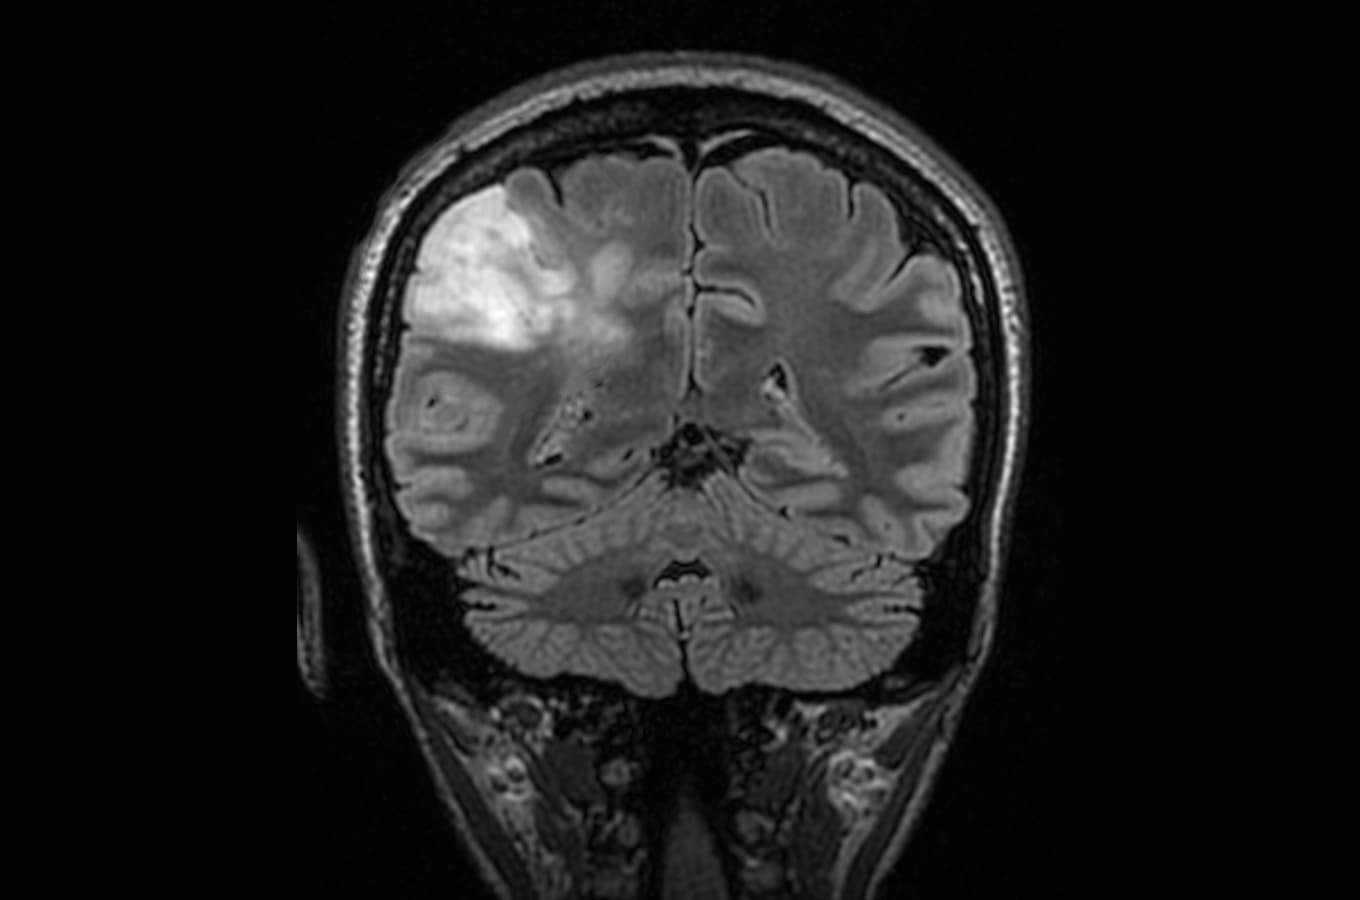

Microbleeds may worsen outcome after head injury National Institute of Neurological Disorders and Stroke

PET Scans & Imaging 101 Imaging Technology News

Mediphany How to read an MRI or CT scan

New technique makes brain scans better, MIT News

Aggressive Surgery Increases Survival with Low-Grade Brain Tumors

Elyse G.'s brain is fabulous. It's also missing a big chunk